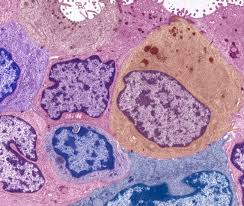

How Are Most Breast Cancers Found / Breast Cancer Survivors World Cancer Research Fund International : Generally, breast cancers are carcinomas.

Genetic mutations on the brca1 and brca2 gene have. Lumps are most likely to be cancerous if they do not cause pain and are hard, unevenly shaped, and immobile. But very few find them while doing bse. But that's not the case. Breast cancer symptoms, breast pain, breast lumps, other changes? Most breast cancer symptoms are discovered by women during regular daily activities like bathing. According to the national breast cancer foundation, 1 in 8 women in the united states will develop breast cancer in her lifetime. Carcinomas are tumors found in the epithelial cells that line organs. Iiic means cancer has been found in 10 or more lymph nodes, or has spread above or below your collarbone. It can be located near the in general, cancerous breast lumps tend to be more irregular in shape. Most breast cancers begin in epithelial cells and form carcinomas. The cancer can spread throughout family history: Find out more about how breast cancer is diagnosed.

Most breast cancers begin in epithelial cells and form carcinomas. How is breast cancer found? how many women get breast cancer? lifestyle changes to consider during and after treatment, moving. Breast cancer is the most common cancer afflicting women in the united states, regardless of race or ethnicity. They may refer women to a breast specialist or a surgeon. When breast cancer is found early, women have many more treatment options compared to when breast cancer is found at a later stage.